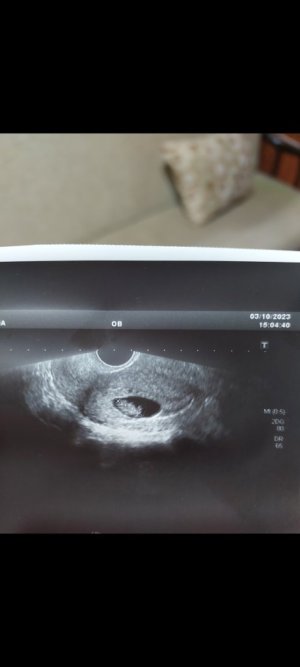

Bana da yorum lütfen karından 10 haftaCanım göbekten bakildiysa erkek

Merhaba sizce nedirRamzi teorisine göre kız gibi duruyor. cinsiyetiniz belli oldu mu acaba ?